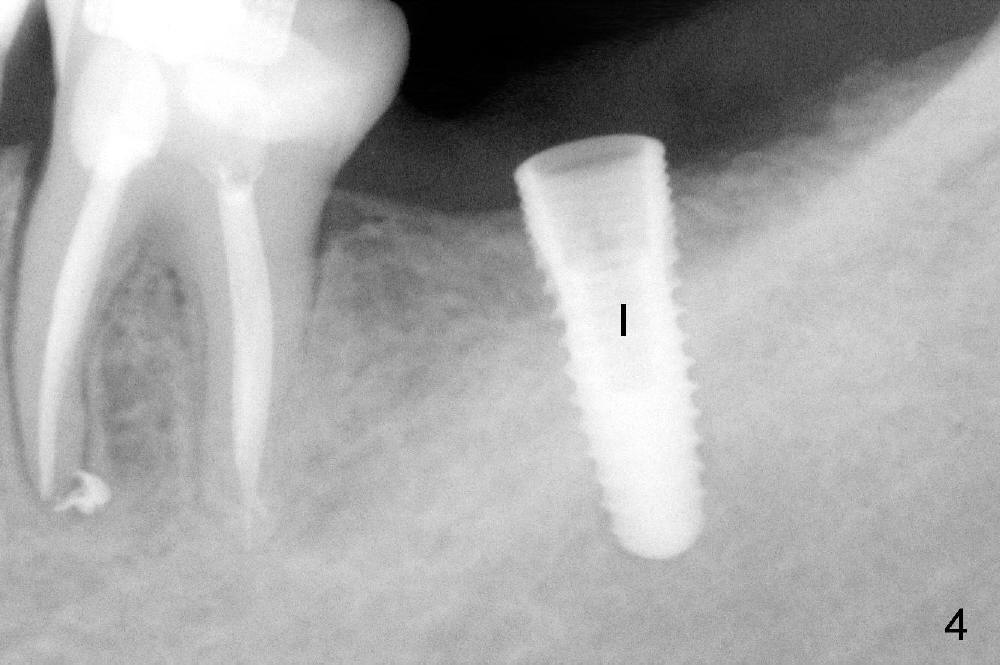

Planning gives the surgery and assistants confidence. Implant placement seems to be more smoothly. A preop PA (Fig.1) shows that the periapical radiolucency of the neighboring tooth #19 disappears. Removal of the residual roots of the teeth #17 and 18 (Fig.1 *) gives rise to a nice surgical field (Fig.2, the sockets packed with Clindamycin soaked gauze). Immediate implant osteotomy is formed as mesial as possible of the wound. Attention is being paid to buccolingual trajectory when the first pilot drill is used (not shown). An intraop PA is taken with a 3.8 mm tap in place to confirm the depth of the osteotomy relative to the inferior alveolar canal (Fig.3). A 4.5x12 mm implant is placed as planned (Fig.4). The elongated wound (mesiodistally) allows the wound to approximate around the implant/healing abutment with sutures (Fig.5). The gingiva heals 8 days postop (Fig.6). The 1st 4 coronal threads remains outside the bone 3.5 months postop (Fig.7 >). It appears that less thread exposure 1 year 7 months postop (Fig.8), suggesting bone growth. To prevent periimplantitis and facilitate restoration, place 2nd molar implant as deep as possible with slightly shorter implant.